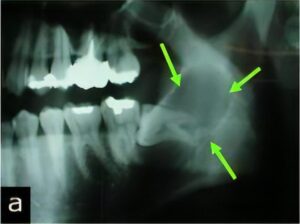

のう胞

のう胞は、何らかの理由で“水を含んだふくろ”ができてしまう病気です。特に顎骨は、のう胞ができやすいと言われています。

顎骨ののう胞では、虫歯から発生する「歯根嚢胞」が大半を占めていますが、くちびるにできる「粘液嚢胞(唾液が貯まった嚢胞)」や「含歯性嚢胞(埋伏歯にできる)」など様々な種類があります。

当科ではCT、MRI、病理組織診(良性悪性の確認検査)などの検査・診断、および治療(手術)を行っています。